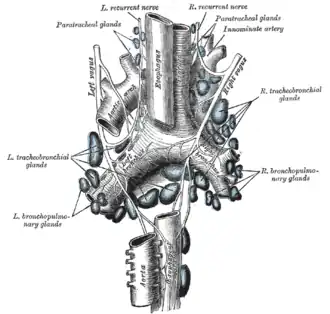

The tracheobronchial lymph glands

The tracheobronchial lymph glands -